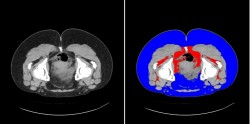

実際にCT画像を撮ってみました。

モデルは20代女性で体重78kgです。

青い部分が脂肪層で、赤が内臓脂肪、グレーが筋肉です。

やはり脂肪層が目立ちますね。